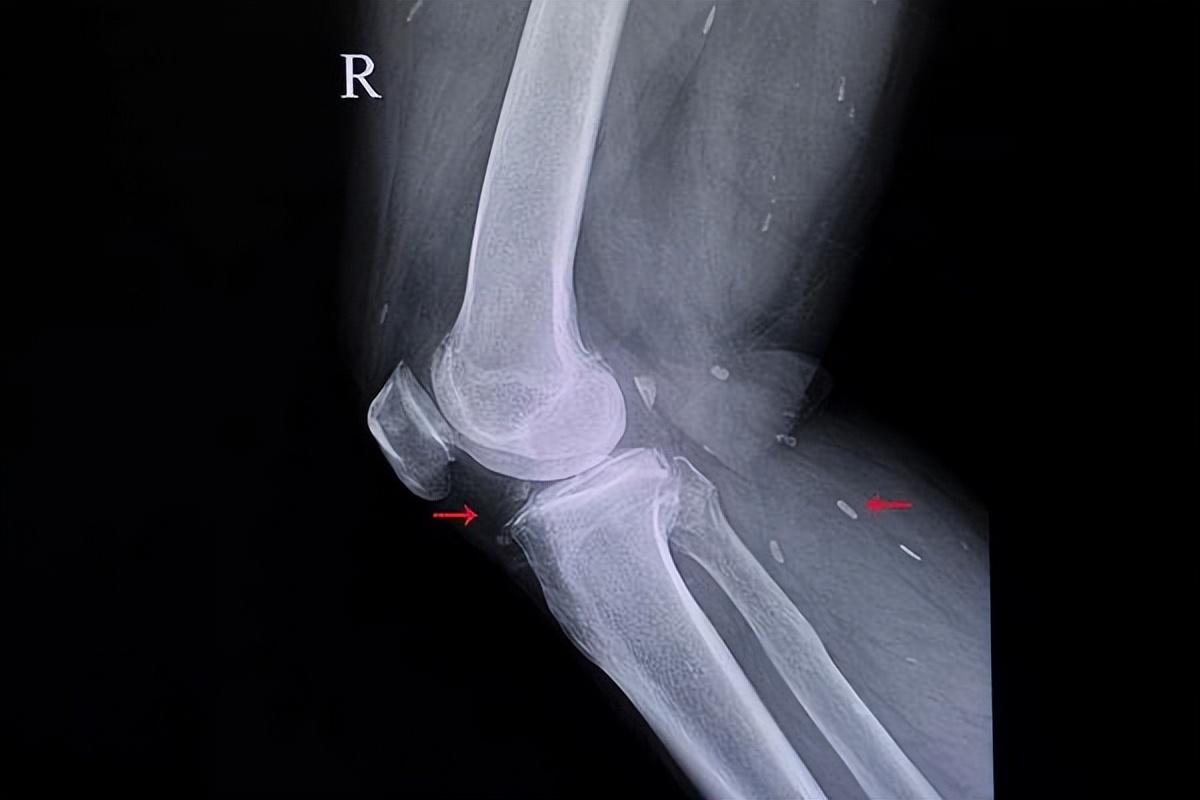

钙在人体内是以离子的形式存在的,当其余负价的离子结合时,就会形成钙盐。

这些钙盐会在人体内不断地沉积,最终导致软组织钙化,给人体带来伤害。

大多数人对钙化这个医学术语都比较陌生,因为钙化并不是特别严重的疾病,所以他们并不会把钙化放在心上。

事实上,钙化是一种特别常见的生理现象,通常情况下,只要患者的钙化不严重,没有影响到患者的正常生活,就不需要进行特殊的治疗。

但少数患者的钙化组织比较特殊,如果没有及时地去医院进行治疗,就容易使患者的身体受到损伤,使患者的生活质量下降。

如果你的钙化发生在以下这3个组织中,就需要尽快地咨询医生,并在医生的指导下进行治疗,才能让其对身体的损害降到最低。